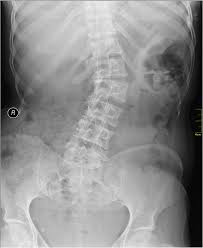

Junho é o mês de conscientização da Escoliose

Junho é o mês de conscientização sobre a escoliose, uma patologia da coluna vertebral que pode comprometer o funcionamento adequado do organismo, causando complicações funcionais e também estéticas. De acordo com a Organização Mundial da Saúde (OMS), a escoliose acomete cerca de 2% a 4% da população mundial, sendo que a grande maioria dessas pessoas está na fase da adolescência.

Segundo o ortopedista especialista em coluna, membro titular da Sociedade Brasileira de Ortopedia e Traumatologia (SBOT) e da Sociedade Brasileira de Coluna (SBC), Djalma Amorim Jr., a escoliose é um encurtamento da coluna causado por uma curvatura lateral. “Normalmente, a coluna vertebral é reta e alinhada. Quando o paciente tem escoliose, a coluna acaba fazendo uma curva para um dos lados, em forma de “C” ou “S”, o que pode causar uma série de complicações.

O ortopedista explica que a escoliose mais comum é a idiopática. “É o tipo que chega com mais frequência ao consultório. Na maioria das vezes, é indolor, mas pode ser dolorosa quando existem deformidades muito elevadas, que acabam comprometendo a função respiratória e a função cardíaca”.

Nos estágios iniciais, a escoliose pode ser tratada de forma não cirúrgica, com o uso de coletes. Entretanto, em casos de uma curvatura mais acentuada, a cirurgia de correção pode ser a única opção. “É muito importante que esse paciente busque uma avaliação correta com especialistas, fazer exames de imagem e, com isso, definir qual o melhor tratamento para o seu caso”, afirma o médico.

Djalma ainda reforça que o diagnóstico precoce pode evitar a necessidade de uma intervenção cirúrgica e garantir um tratamento mais conservador. “Portanto, a pessoa deve ficar atenta aos seguintes sintomas: gibosidade (proeminência) nas costas; assimetria na cintura; tronco inclinado para um dos lados; mamas assimétricas (meninas); ombros em alturas diferentes; e escápula mais alta em relação à outra”, indica.

A cirurgia para corrigir a escoliose costuma ser indicada em casos mais graves, que podem ser incapacitantes e muito dolorosos, conta o especialista. “Entre as cirurgias de coluna, é uma das técnicas que você tem o melhor retorno do ponto de vista de resultado, porque é possível melhorar o bem-estar do paciente, a autoestima. Eu digo sempre que o tratamento cirúrgico da escoliose é um antes da pessoa e um depois, devido à correção. Então, é uma satisfação que não tem preço”, destaca.